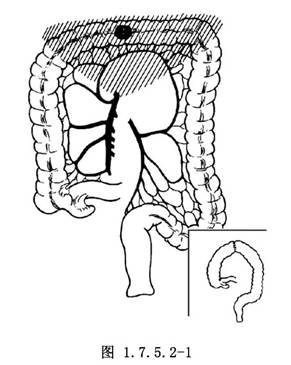

1.橫結腸中部癌,隨中結腸動脈的左、右支轉移至腸繫膜上動脈區淋巴結。手術應將大網膜、橫結腸及其系膜、淋巴結等全部切除,再遊離升結腸及降結腸,做結腸對端吻合(圖1.7.5.2-1)。橫結腸癌常與附近臟器粘連,如胃大彎、小腸等,或浸潤至胰腺體尾部,手術時如有可能應將粘着的組織一併切除。對引起梗阻的晚期癌腫,可做迴腸末端與降結腸或乙狀結腸吻合,以解除梗阻症狀。